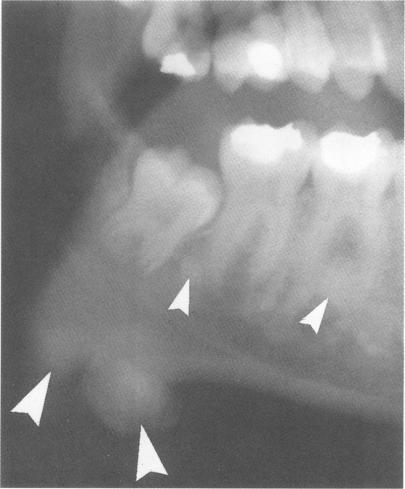

家族性腺瘤性息肉病的牙齿表型:用于牙科全景X线片变化的加权评分系统的诊断应用

The dental phenotype in familial adenomatous polyposis: diagnostic application of a weighted scoring system for changes on dental panoramic radiographs.

A weighted scoring system (Dental Panoramic Radiograph Score) taking into consideration the nature, extent, and site of osseous and dental changes on dental panoramic radiographs in familial adenomatous polyposis is described. The weighting takes into consideration the incidence of the anomaly in the general population. The reliability of the system was tested by application to 85 people known to be affected by clinical or mutation analysis, 30 people lacking mutation in the adenomatous polyposis gene, and 19 people shown to be at low risk (< 1%) by linkage analysis. Using the highest thresholds, a specificity of 100% and sensitivity of approximately 68% was obtained. If all positive findings were considered as significant, sensitivity was increased to approximately 82% but the specificity was reduced to approximately 88%. Significant DPRS findings were observed at a significantly higher frequency in patients aged over 20 compared to the patients aged 20 and under. Overall, approximately 68% of the affected subjects had significant changes, and approximately 18% had normal appearance on DPR, with the remainder having changes classified as minimal or equivocal.

摘要

本文描述了一种加权评分系统(牙科全景X线片评分),该系统考虑了家族性腺瘤性息肉病患者牙科全景X线片中骨与牙齿变化的性质、范围及部位。加权过程考虑了该异常在普通人群中的发生率。通过将该系统应用于85名经临床或突变分析确诊患病的患者、30名腺瘤性息肉病基因突变阴性者以及19名经连锁分析显示低风险(<1%)者,对该系统的可靠性进行了测试。采用最高阈值时,特异性为100%,敏感性约为68%。若将所有阳性结果均视为有意义,则敏感性提高至约82%,但特异性降至约88%。与20岁及以下患者相比,20岁以上患者中观察到显著牙科全景X线片评分结果的频率显著更高。总体而言,约68%的患病受试者有显著变化,约18%的受试者牙科全景X线片表现正常,其余受试者的变化分类为轻微或不明确。